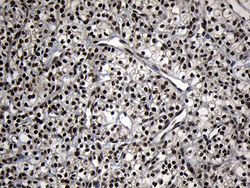

Supportive validation

- Submitted by

- OriGene (provider)

- Main image

- Experimental details

- Immunohistochemical staining of paraffin-embedded Carcinoma of Human kidney tissue using anti-ZNF583 mouse monoclonal antibody.(Heat-induced epitope retrieval by 1mM EDTA in 10mM Tris buffer (pH8.5) at 120°C for 3 min, TA810549)(1:150)

- Validation comment

- IHC